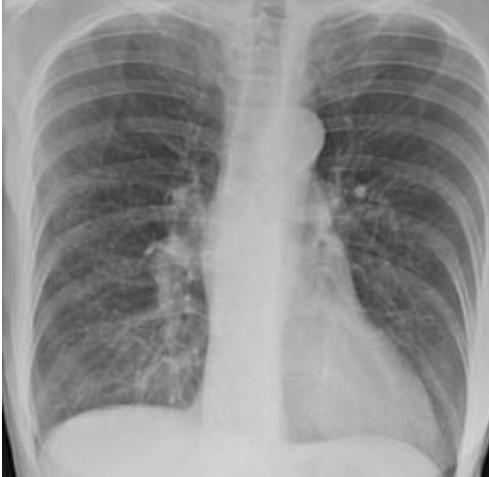

Как пишет Тhe Sun, впечатляющими снимками поделилась доктор Бриттани Бэнкхед-Кендалл, доцент Центра медицинских наук Техасского технологического университета, которая вылечила тысячи пациентов с коронавирусом.

Одно изображение показывает нормальную здоровую пару легких, другое - легкие курильщика, а третье - легкие пациента с коронавирусом.

"Легкие после коронавируса выглядят хуже, чем любой тип легких ужасного курильщика, который мы когда-либо видели. Они разрушаются. И они слипаются. И одышка сохраняется", - сказала доктор.

Бриттани Бэнкхед-Кендалл подчеркнула, что разрушительное действие Covid-19 на легкие заметно даже у тех пациентов, кто перенес его в легкой форме.

Она добавила, что пока неизвестно, заживут ли когда-либо рубцы, вызванные коронавирусом, но каждый, кто испытывает стойкую одышку, должен поговорить об этом со своим врачом.